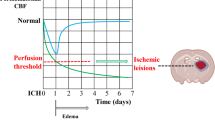

Within the first 6 h of stroke onset, ischemic cell injury is subtle and hard to recognize under the microscope. Functional impairment is obvious, but can be induced by ischemic blood flow allowing recovery with flow restoration. The critical cerebral blood flow (CBF) threshold for irreversible injury is ~15 ml/100 g × min. Below this threshold, ischemic brain tissue takes up water in case of any residual capillary flow (ionic edema). Because tissue water content is linearly related to X-ray attenuation, computed tomography (CT) can detect and measure ionic edema and, thus, determine ischemic brain infarction. In contrast, diffusion-weighted magnetic resonance imaging (DWI) detects cytotoxic edema that develops at higher thresholds of ischemic CBF and is thus highly sensitive for milder levels of brain ischemia, but not specific for irreversible brain tissue injury.

The concept of thresholds of ischemia in relation to brain structure and function was introduced in 1977 [18, 19] and became the rationale for reperfusion therapy by showing that the critical cerebral blood flow (CBF) threshold for irreversible injury is lower than for neuronal dysfunction. Cortical evoked potentials’ amplitude diminished immediately with a residual CBF of <16 ml/100 g × min and became zero with lower CBF values. Animals with permanent MCA occlusion were followed during 3 years and then sacrificed. It turned out that the tissue volume with initial loss of cortical function exceeded the tissue volume of final brain infarction. The authors concluded that “the ultimate area of infarction is confined to areas where blood flow reduction in the acute stage of the stroke is a great deal more intense and certainly below values of 10 ml/100 g × min” [18]. Astrup et al. showed that massive release of intra-cellular potassium ions into the extra-cellular space does not explain the failure of neuronal function occurring at lower cortical CBF at about 6 ml/100 g × min [19]. They proposed the concept of “ischemic penumbra during which the neurons remain structurally intact but functionally inactive” after finding that an increase in CBF can restore evoked potential and normalize extra-cellular potassium activity [20]. This concept was widened by studies showing that neuronal survival under ischemic conditions depends on time [21, 22]. At CBF below 10 ml/100 g × min, neurons die within 30 min, but survive indefinitely at a CBF above 15 ml/100 g × min. Awake non-human primates can tolerate brain ischemia of 10 to 15 ml/100 g × min for 2 to 3 h without irreversible injury. The concept of the viability thresholds of brain ischemia became more complex after the study of additional metabolic disturbances in brain ischemia. Table 1 summarizes the most important electro-physiological and metabolic changes at different ischemic CBF thresholds according to Hossmann [14].

Ionic edema means net uptake of water by dense ischemic brain tissue from perfused or re-perfused capillaries through an intact blood-brain-barrier. Depletion of extracellular Na+ due to cytotoxic edema creates a concentration gradient between intravascular and extracellular compartments across the blood-brain-barrier. Along this osmotic pressure gradient, Na+, Cl−, and water molecules are transported into the extracellular space through special endothelium channels (permeability pores) that can be blocked with low-dose glibenclamide [29]. Net water uptake starts immediately after MCA occlusion and was related to the degree of ischemia in that region if CBF was reduced below 15–20 ml/100 g × min [30]. Cerebral water content increased from 78 to 80.5% within 3 h of permanent arterial occlusion and up to 83% within 9 h. Restoration of blood flow following 30-min occlusion stopped the increase in cerebral water content and reached the control value after 3 days [31]. In a rat model of global ischemia down to 5.8 ml/100 g × min, cortical specific gravity decreased from 1.0484 to 1.0445 within 60 min and recovered with restoration of CBF after 15 min of ischemia, but not after 30 or 60 min of ischemia [32]. After MCA occlusion in the cat, cortical water content increased from 80.5 to 84% in regions with CBF below 10–15 ml/100 g × min. Ionic edema was associated with further decrease in CBF below the threshold of 10 ml/100 g × min defined as “critical ischemia” below which functional recovery is impossible [15]. Ionic edema is, therefore, an early marker of irreversible ischemic injury.

Focal brain ischemia with CBF <25 ml/100 g × min causes neuronal dysfunction and cytotoxic edema being detected by DWI with high sensitivity. As long as CBF does not fall below ~15 ml/100 g × min (“critical ischemia”), brain tissue can recover with restoration of CBF. In areas with critical ischemia, cytotoxic edema is associated with ionic edema meaning net uptake of water if capillaries provide residual flow. Ionic edema with the increase in tissue water content is the specific marker of brain tissue with almost no chances to survive even with reperfusion. Moreover, delayed reperfusion of brain tissue with critical ischemia may enhance ionic and later vasogenic edema and mass effect. No randomized controlled trial has shown so far that patients with extended ionic edema benefit from reperfusion therapy. Computed tomography is accurate in detecting ionic and vasogenic edema and capable of quantifying changes in brain tissue water content. The comparison of the diagnostic accuracies of CT and MRI requires an exact definition of the object under observation. Both modalities do not diagnose the clinical entity “stroke,” but aspects of the underlying pathology. Moreover, both modalities are complementary in imaging two different aspects of acute ischemic brain tissue, the potentially reversible cytotoxic edema and the ionic edema indicating irreversible damage.